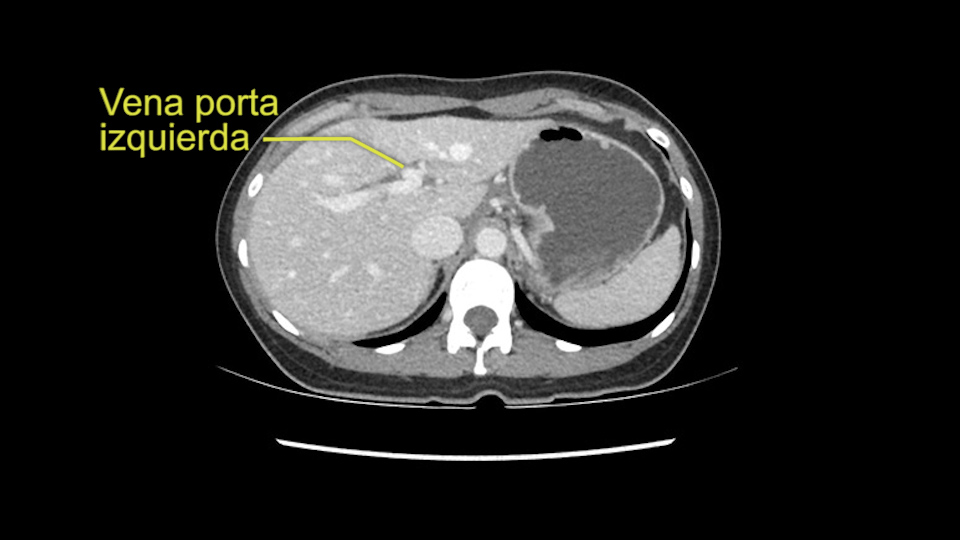

So the issue with regards to resection. A left sided tumor. I believe I can see the falciform ligament right here so we’re looking at a resection of Segments 2, 3 of the left lobe of the liver. The left portal vein is right there. I think we’ll be wiser to take the left portal vein and therefore get well into Segment 4 and do a left hemihepatectomy. Certainly, one does not need to take the middle hepatic vein; it’s miles from the tumor.

My plan would be to leave the caudate lobe intact. You usually have to divide the caudate branches. I can see one of the caudate branches here coming off the left portal vein. You usually have to take that to get adequate length although you might be able to divide the portal vein past that left caudate branch.

Now let’s look at some specific anatomical points for planning this surgery. First thing you see when you see a left hemihepatectomy is that where is the left portal vein and the right portal vein branching? And what is the stump of the left portal vein available for you for ligation? In this particular case, you’ll find that there’s overhanging of the tumor but left portal vein pedicle is sufficiently available for us for ligation.

En cuanto a la hepatectomia izquierda aquí creo que la clave va a ser disecar bien el ligamento venoso y poder ir pasar una cinta alrededor de la vena hepática izquierda, en este caso parece que al vena hepática izquierda está muy junta, como en muchos casos a la vena hepática media, a ser importante disecar bien la vena supra hepática izquierda para poder pasar alrededor de ella sin dañar la cava o la vena hepática media. Una vez que hayamos hecho esto pasaremos a mirar la porta, y yo siempre tiendo a disecar las estructuras lo mas próximas al hígado posible, disecaremos la arteria hepática media rama del segmento 2-3 y la rama del segmento 4 si estamos haciendo una hepatectomia izquierda, y insisto parce que este tumor además tiene otras muchas ramas que van directas al tumor que habrá que ligar, eso nos dará acceso a la vena porta izquierda que probablemente resecare con una grapadora lineal, y finalmente transectarmos, haremos la transeccion hepática.